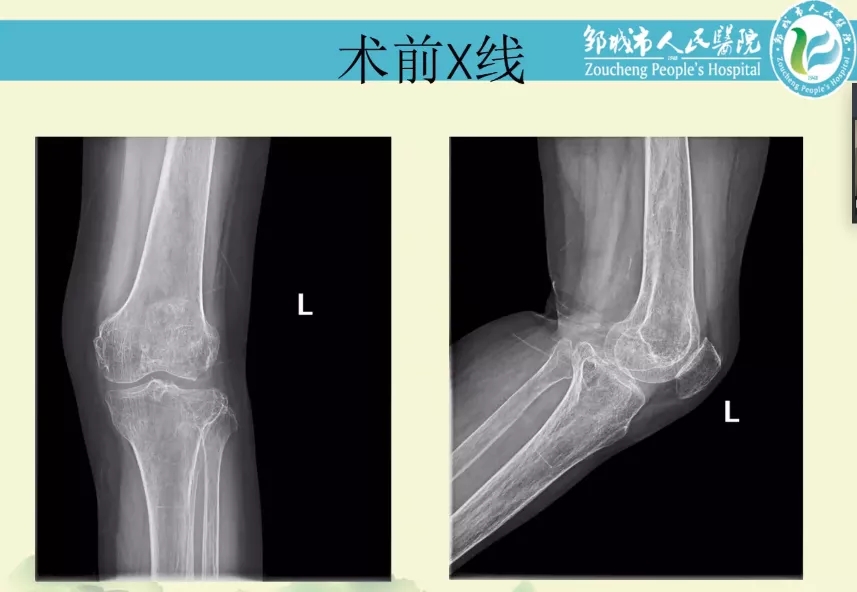

孙永强教授和袁振教授就胫骨骨缺损处理、假体选择时是否应使用延长杆、术中应使用双侧同期还是双侧分期更好等问题进行了倾囊相授,并给予手术治疗上的建议。随后由山东省邹城市人民医院纪建军主任带来第二则病例分享。患者情况:中年女性,有高血压、糖尿病既往史,因左膝外伤后疼痛、活动受限1年入院。查体:左膝轻度外翻畸形,无明显肿胀,皮肤无红肿、破溃,左膝外侧压痛明显,髌骨研磨试验(+),侧方应力试验(-),膝关节活动范围约为0°-120°,足趾感觉及血运正常。入院诊断:1.左膝创伤性关节炎;2.左胫骨平台陈旧性骨折;3.高血压病;4.糖尿病;5.骨质疏松症。

对此病例,孙永强教授和袁振教授就合并严重骨质疏松症患者术中关注点和术后功能锻炼进行等问题给出建设性指导。最后由孙永强教授进行了简短的课程总结,本期空中科室会分享了很多实用的临床经验,干货满满,在手术中存在的困惑与不解都迎刃而解。力达康学院诚心邀请更多骨科专家医生参加空中科室会,分享经典病例,交流手术心得,将知识共享进行贯穿,令TKA越来越完美。